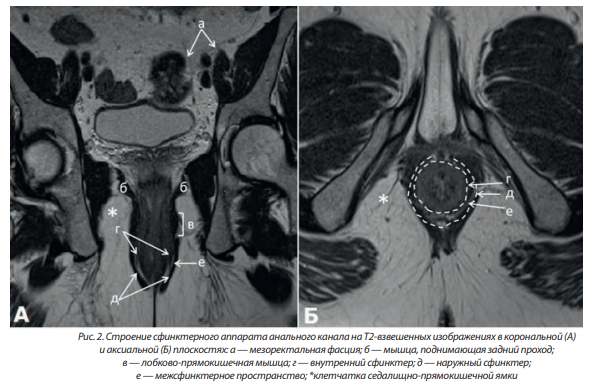

Мышечные структуры прямой кишки представлены внутренним и наружным сфинктерами. Внутренний сфинктер протяженностью 2,5–4 см, образован утолщением дистальной части внутреннего циркулярного слоя мышечной оболочки прямой кишки и является его продолжением. Он представлен гладкой мышечной тканью и визуализируется на корональных изображениях в виде слоя толщиной 0,3–0,4 см. Внутренний гладкомышечный сфинктер окружен наружным сфинктером, состоящим из поперечно-полосатых мышц. Пальпаторно можно определить границу между внутренним и наружным сфинктерами в виде межфасциальной борозды. Поверхностный слой наружного сфинктера сзади прикреплен к заднепроходно-копчиковой связке, а глубокий слой является продолжением лобково-прямокишечной мышцы.

Между внутренним и наружным сфинктером расположено межсфинктерное пространство, образованное наружной продольной мышцей прямой кишки (мышцей Трейца). Порции этой мышцы пронизывают внутренний сфинктер и заканчиваются в подслизистом слое прямой кишки. Морфологически он представляет собой клетчатку и содержит терминальные волокна продольного слоя собственной мышечной оболочки прямой кишки. Наиболее отчетливо этот слой визуализируется на корональных Т2-взвешенных МР-изображениях в виде светлой полоски толщиной 0,1–0,2 см (рис. 2).

Внешняя мышечная оболочка анального канала состоит из поперечнополосатой мышечной ткани; в верхней части она представлена волокнами лобково-прямокишечной мышцы, а в нижней — наружным сфинктером. Лобково-прямокишечная мышца является главным компонентом сфинктерного комплекса; она представляет собой утолщение мышц тазового дна протяженностью ~1,0 см на уровне дистального прикрепления мышц, поднимающих задний проход, и больше выражена у мужчин. Волокна лобково-прямокишечной мышцы вплетены в воронкообразную дистальную часть m. levator ani, которая, в свою очередь, прикрепляет сфинктерный комплекс к стенкам таза.